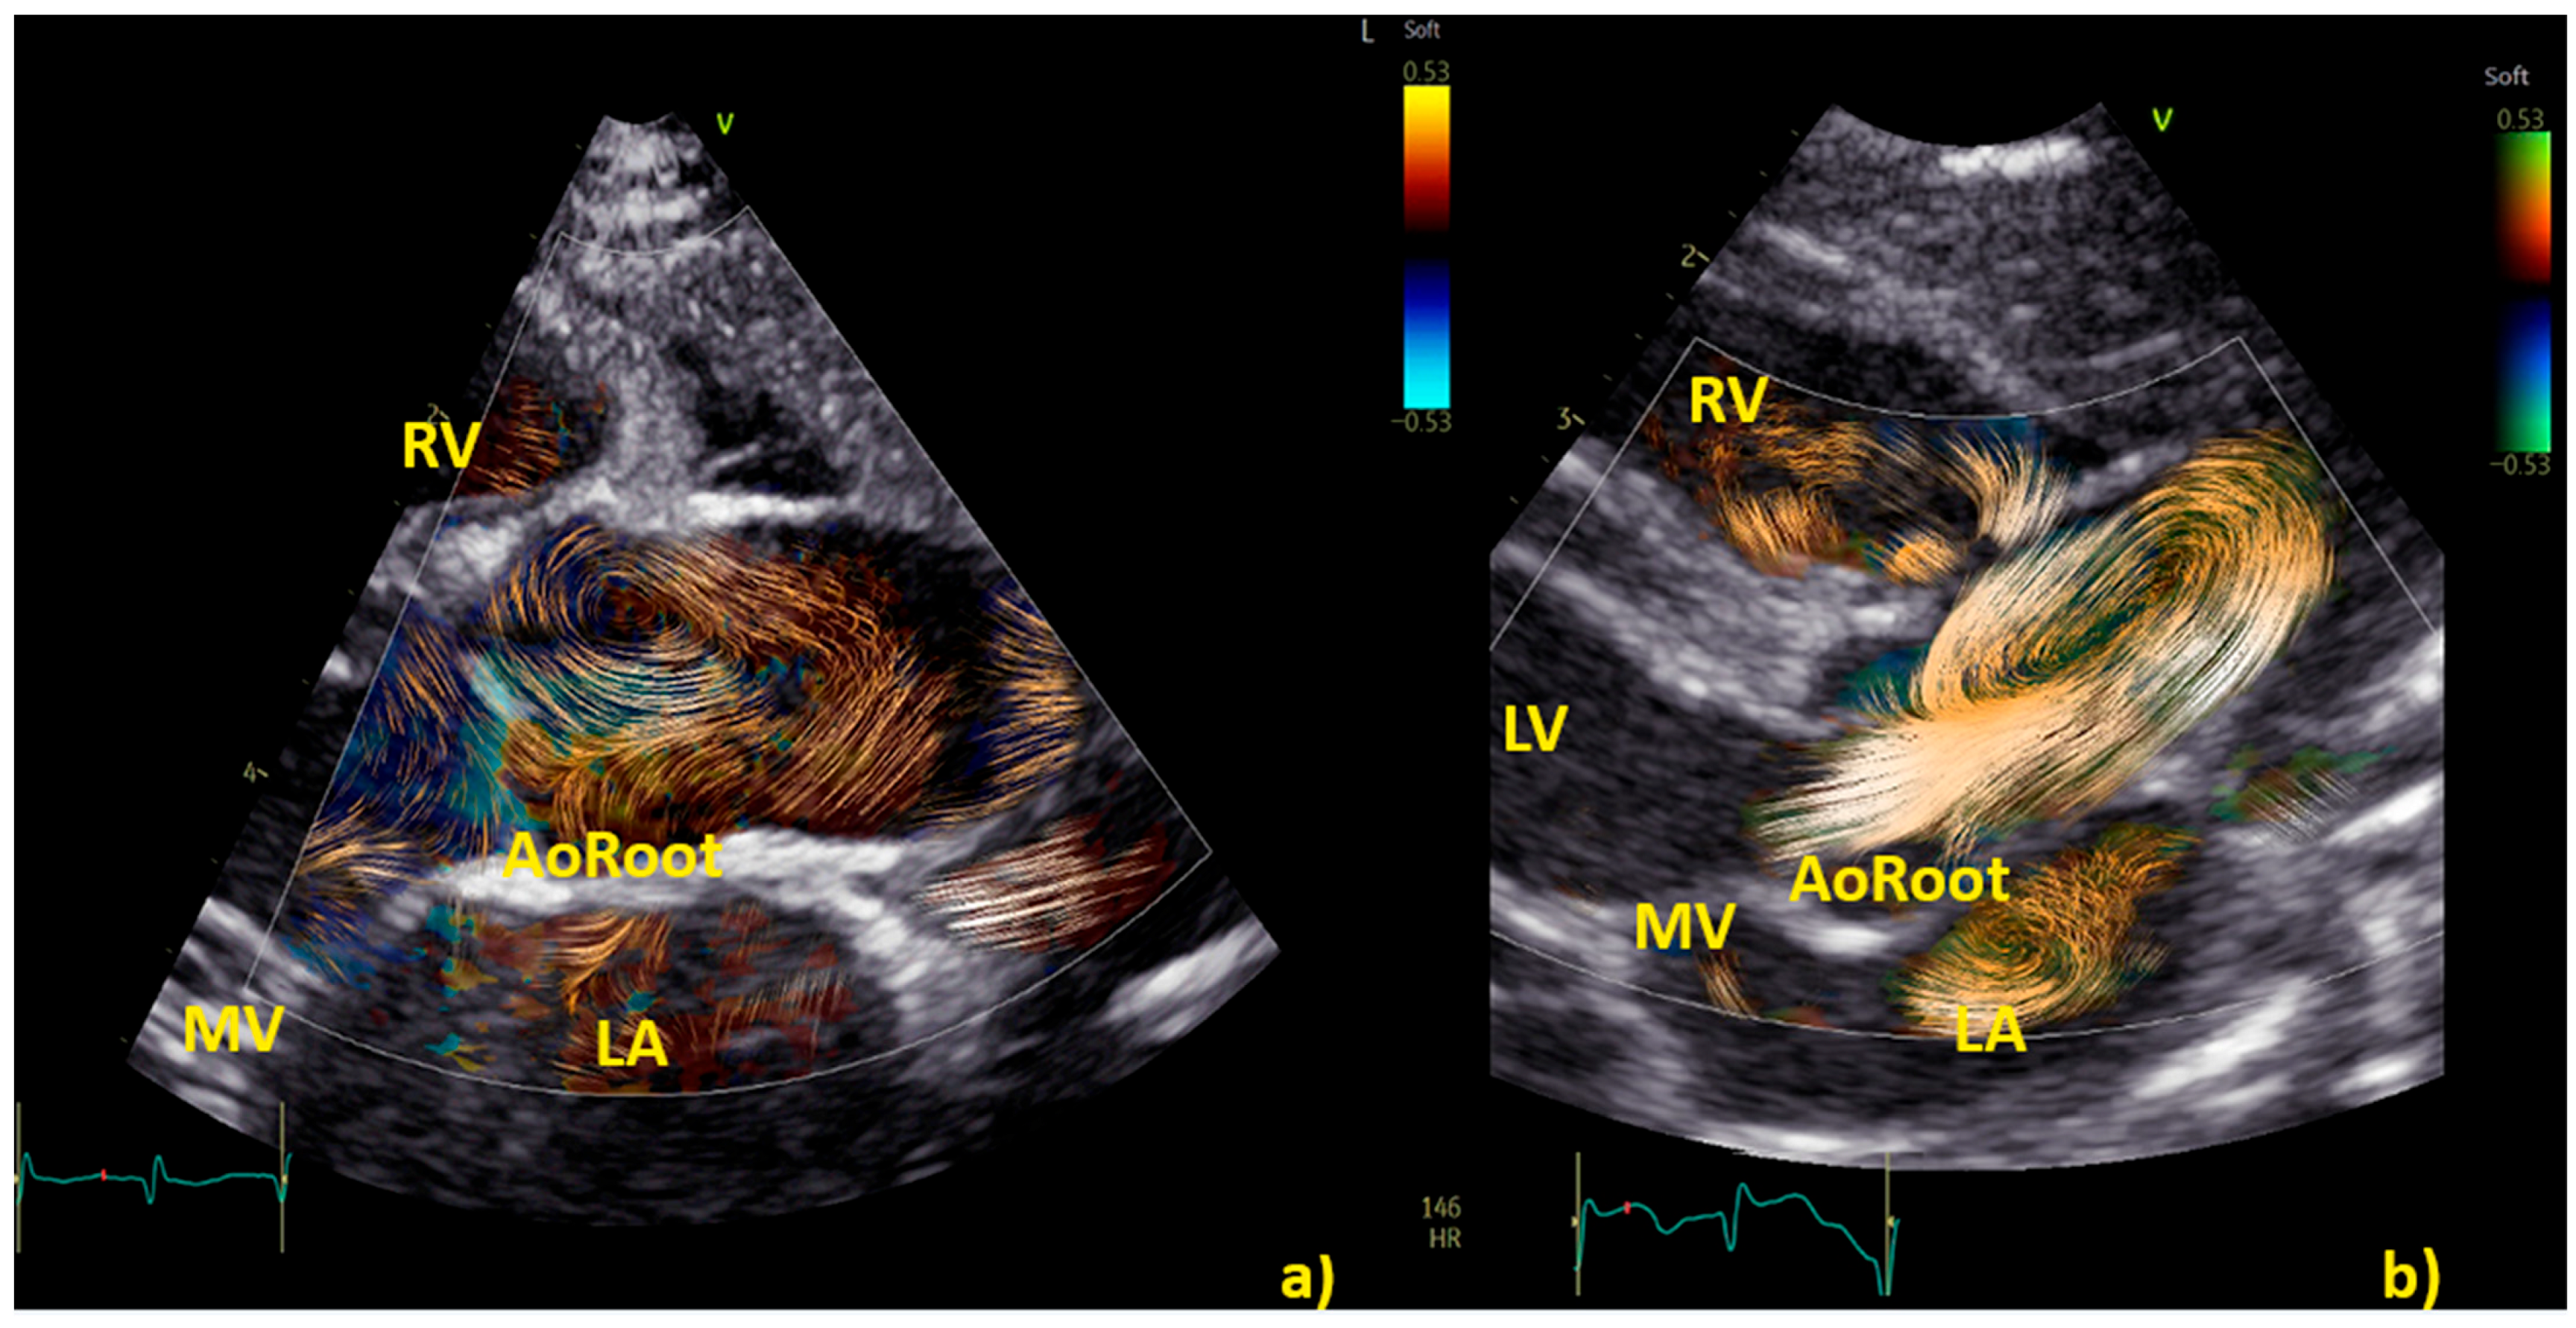

Application of BST echocardiography for the evaluation of aortic flow in children is still limited but promising [8]. In 100 healthy children [19], specific patterns of aortic flow by BST were observed. Initially, in early systole, the flow in the aortic root is laminar; however, in mid-systole, the flow splits into two helical branches going in opposite directions (one to the right ascending aortic wall and the other toward the left aortic wall) and vortices form close to the sino-tubular junction [19]. Finally, the flow returns laminar during late systole [19]. This pattern is described in Figure 4.

Figure 4. The three different phases of aortic flow in a healthy child. The first phase is shown in the left picture (a), where the blood flow is laminar in the aortic root. Both second and third phases are shown in the picture on the right (b): double helical flow (with a right–handed branch (RHB) to the left aortic wall, and a left–handed branch (LHN) to the right aortic wall) and laminar in ascending aorta. BST was performed from a focused and zoomed view of the aortic root and the ascending aorta. The color Doppler sector with BST was positioned over the aortic root in the parasternal long-axis view and the ascending aorta in the suprasternal view. Acquisitions included at least 2 cardiac cycles at a range of 380 to 560 frames per second with Nyquist limits ranging from 53 to 58 cm/s.